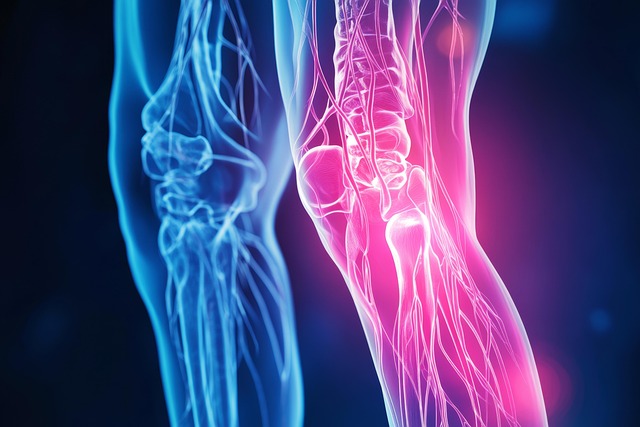

무릎통증 치료방법, 단계별 접근이 필요

통증의 원인과 정도에 따라 치료는 다양하게 구성된다.

- 약물치료: 비스테로이드성 소염제(NSAIDs), 근육 이완제, 국소 진통 패치 등을 사용

- 물리치료: 냉온 찜질, 전기자극, 레이저 치료 등으로 통증 완화 및 회복 도모

- 운동요법: 대퇴사두근 강화운동, 수영, 실내 자전거 등의 무릎부하 감소 운동 병행

- 주사치료: 스테로이드, 히알루론산, PRP 등 관절내 주사 치료 가능

- 수술치료: 연골 손상이 심각하거나 보존 치료 효과가 없을 경우 관절경 수술 또는 인공관절 수술 시행